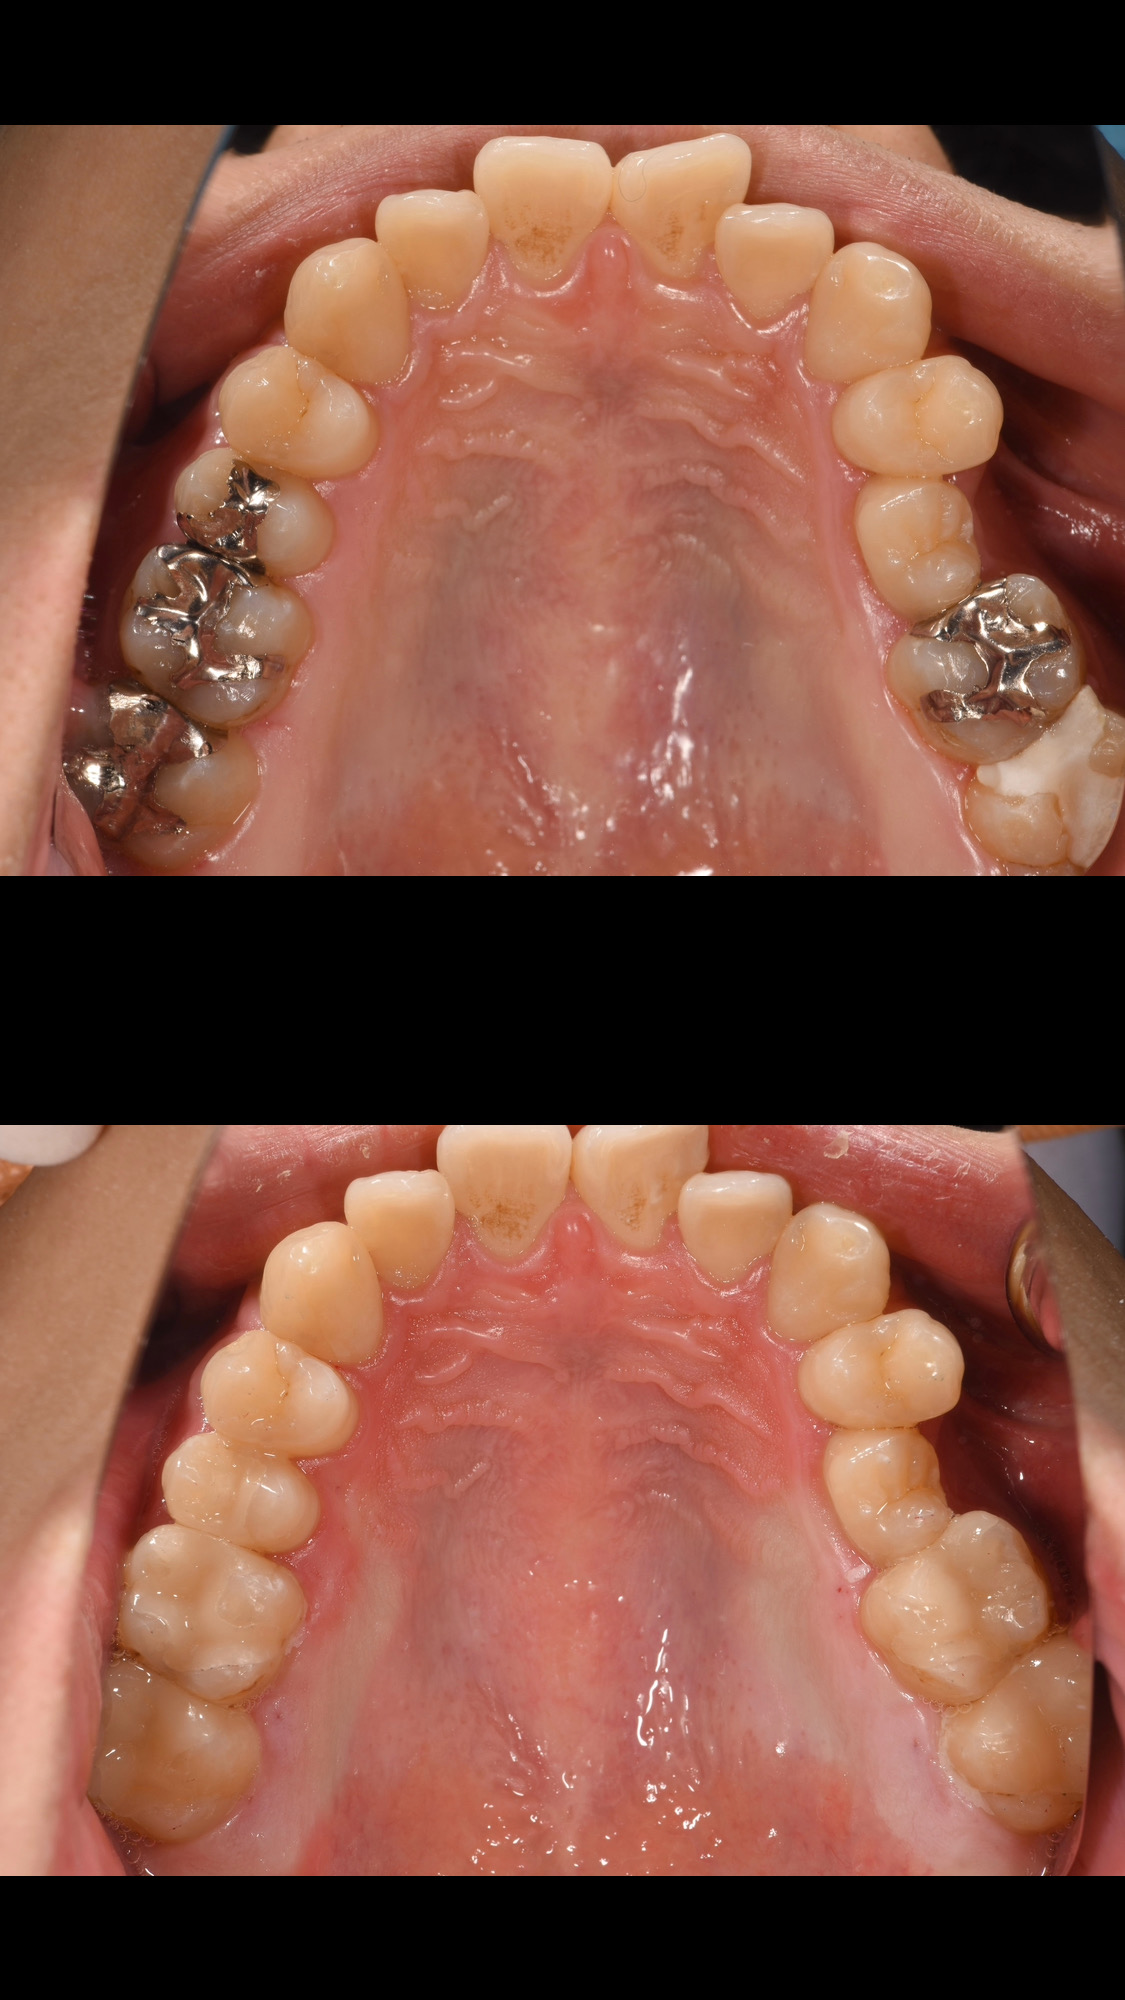

• 銀歯をセラミックインレーに

銀歯をセラミックインレーに